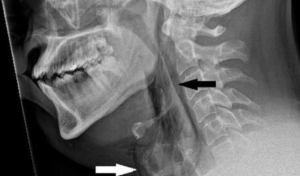

جنهن فوري بعد مريض جو ايڪسري ڪيو ويو جنهن سان انڪشاف ٿيو ته ساهه جي ناليءَ ۾ سوراخ ٿي ويو آهي.

ان کان پوءِ سي ٽي اسڪين مان خبر پئي ته ساهه جي نالي ۾ 2 ملي ميٽر وڏو ۽ 5 مليميٽر گھرو سوراخ ٿي ويو آهي.